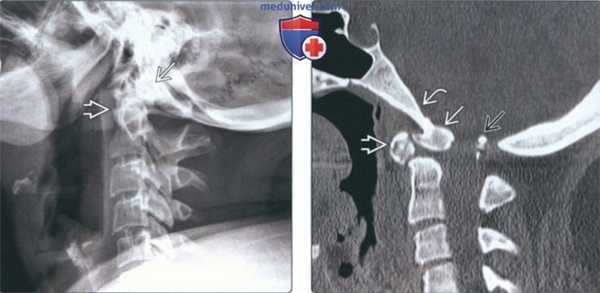

(Слева) На рентгенограмме шейного отдела позвоночника в боковой проекции (нейтральное положение) визуализируется дистопическая зубовидная кость, слившаяся со скатом. Также определяется гипоплазия зубовидного отростка.

(Справа) На сагиттальной КТ в костном окне визуализируется зубовидная кость, слившаяся в единое целое со скатом. Определяется ремоделирование передней дуги С1 и зубовидной кости наряду с гипоплазией задней дуги С1, находящейся в позвоночном канале сразу же под большим затылочным отверстием.

2. Рентгенография при птичьей кости:

• Рентгенологические признаки:

о Четко очерченная кость, слившаяся со скатом:

- Зубовидный отросток обычно короче, чем в норме

- ± увеличение передней дуги С1

3. КТ при птичьей кости:

• КТ в костном окне:

о Картина аналогична таковой на рентгенограммах

о Часто наблюдается дисплазия ската

(Слева) На корональной КТ в коаном окне определяется слияние дистопической зубовидной кости со скатом (эксцентрически смещенным вправо).

(Справа) На аксиальной MPT (Т2) определяется патологический сигнал высокой интенсивности в шейном отделе спинного мозга на уровне С1, отражающий его повреждение, обусловленное атланто-аксиальной нестабильностью и легкой гипоплазией С1 в сочетании с эксцентрической птичьей костью.